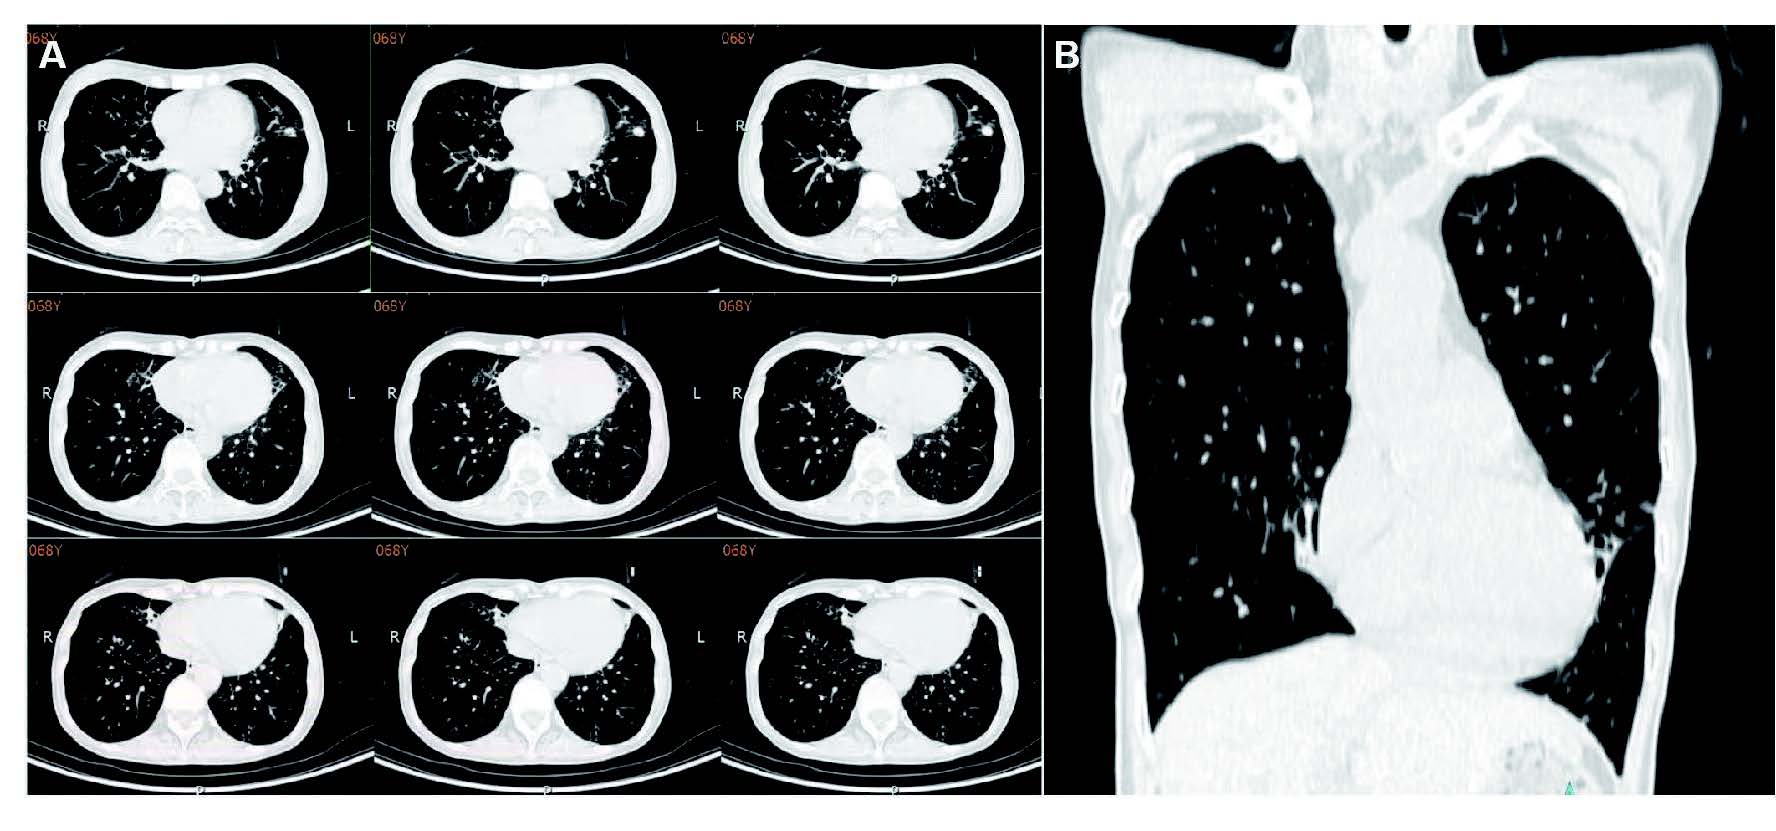

After five days, the patient underwent electronic bronchoscopy which showed normal vocal cords, trachea, and bronchus. Main carnia appeared sharp and bilateral bronchial tree were unobstructed. Mucosa was smooth without any hemorrhage but with abundant mucus (Figure 2). Bronchoalveolar lavage fluid (BALF) sample was extracted by brushing at middle lobe of the right lung. It was then examined by AFB smear, polymerase chain reaction (melting curve method), Xpert MTB/RIF (Xpert MTB/RIF assay is an automated, single-cartridge-based nucleic acid amplification test that is able to simultaneously detect M. tuberculosis and rifampicin resistance within 2 to 3 hours), bacterial and fungi culture. The results were all negative except AFB which was positive (2+). The sputum collected after bronchoscopy was also positive (1+). Unbiased metagenomics next generation sequencing (mNGS) of the BALF identified 42 sequence reads corresponding to Pseudomonas aeruginosa (PA) and 74 sequence reads corresponding to mycobacterium intracellularis (Table 1).

Figure 2

Figure 2: Electronic bronchoscopy which showed normal vocal cords, trachea and bronchus. Main carnia appeared sharp and bilateral bronchial tree were unobstructed. Mucosa was smooth without any hemorrhage but with abundant mucus.